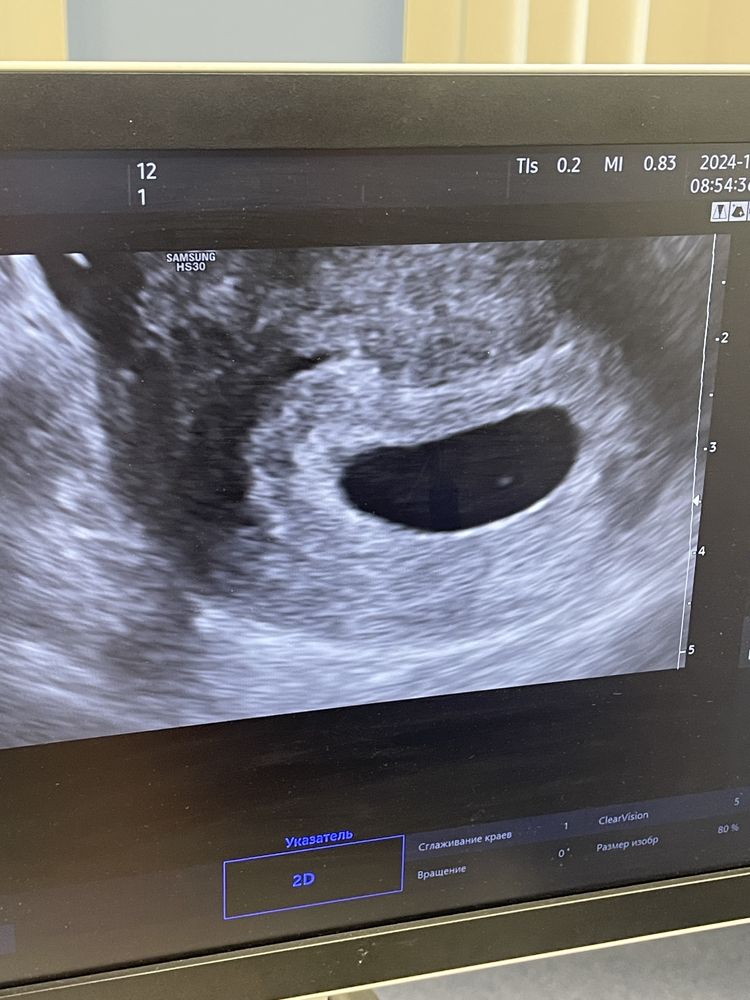

Узи 7,3 (6,5)

У кого так же было? Отправили на контрольное узи через 10 дней, ничего не беспокоит. Чистку будут делать если 16 числа ничего не найдут.

Пя большой уже и если бы был эмбрион, то 100% увидели бы хоть что-то, хотя бы намек, а тут на всех фото видно невооруженным глазом-пусто..